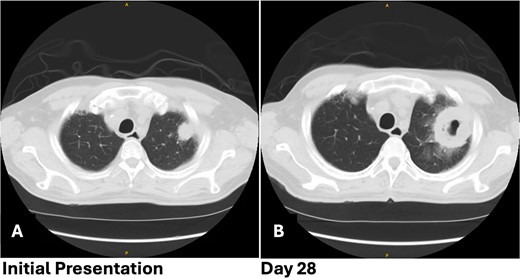

After 2 days, a follow-up chest X-ray showed a more prominent-appearing lung mass, prompting the ordering of a chest computed tomography (CT) scan. The CT scan revealed a focal mass-like consolidation measuring 2.4 × 2.2 cm in the LUL (Fig. 1A). Further infectious work-up including fungal antigen markers for Aspergillus, histoplasmosis, and blastomycosis were negative. His COVID-19 symptoms improved, so he was discharged home with close follow-up.

Patient 1 pre-operative images showing rapid progression of disease. (A) Initial CT scan with a 2.4 cm LUL pulmonary nodule. (B) Repeat CT scan 28 days later showing rapid growth and cavitation of the mass, now measuring 7.1 cm.

The patient returned with hypotension, weakness, and a presyncopal episode secondary to Clostridium difficile infection and dehydration. Chest imaging showed further growth of the LUL mass now up to 7.1 cm with cavitation from 4 weeks earlier (Fig. 1B). A flexible bronchoscopy was performed and samples sent for pathology and microbiology. This revealed extensive tissue necrosis and fungal hyphae consistent with mucormycosis.